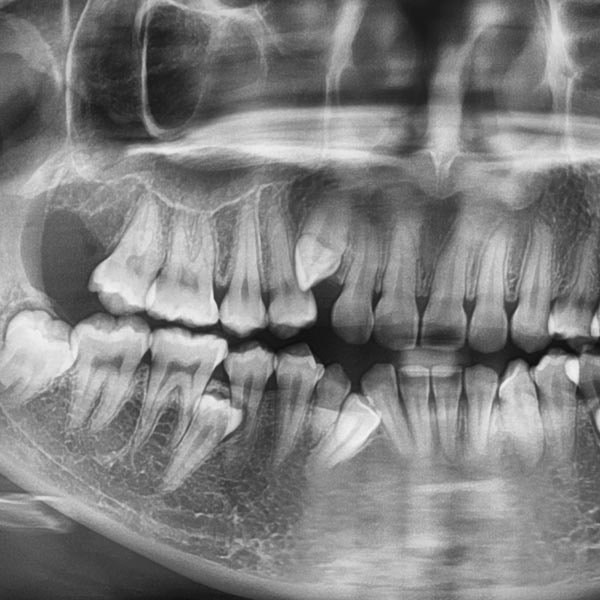

- High-resolution imaging for safer extractions

From routine removals to impacted wisdom teeth, Dr. Sasan Khodabakhsh and his team handle every kind of extraction with skill and precision.

Do I Need a Tooth Extraction?

Severe pain, gum swelling, and visible tooth fractures can all be indicative of a serious dental problem. However, there is no way to know for sure if you need extraction unless you see a dentist for an exam.